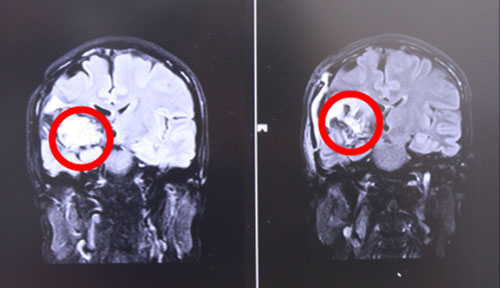

左側(cè)為術(shù)前,右側(cè)為術(shù)后,術(shù)后紅圈內(nèi)腫瘤物基本消失

17號上午9點左右,張XX被推入手術(shù)室,在全麻狀態(tài)下接受“右顳頂海綿狀血管瘤切除術(shù)”。至手術(shù)結(jié)束,已經(jīng)日暮時分。手術(shù)由經(jīng)驗豐富的侯增欣主任主刀,上顯微鏡,分離側(cè)裂,保護血管,切開顳上回皮質(zhì),見腫物呈暗褐色,靠近側(cè)裂動脈,并向大腦深部丘腦生長,術(shù)中顯微鏡下腫物近全切除,手術(shù)順利,腦神經(jīng)及血管保護完好,患者全麻醒,返ICU病房進行術(shù)后監(jiān)護。

術(shù)后,患者頭暈癥狀好轉(zhuǎn),面部抽搐也未發(fā)作,肢體功能明顯好轉(zhuǎn),生命體征平穩(wěn)。據(jù)侯主任介紹,經(jīng)過一段時間的康復(fù),患者即可恢復(fù)生活自理能力。目前患者已經(jīng)出院。針對此次案例,侯主任語重心長地說,作為一名神經(jīng)外科醫(yī)生,不僅要做好每一個手術(shù),確;颊呱踩那疤嵯拢M可能全切腫瘤。更重要的是要針對每位患者的特殊情況特殊對待,拿捏好手術(shù)的度,不能一味保守或者冒進地對腫瘤不作為或不管不顧全切。侯主任根據(jù)自己臨床多年的經(jīng)驗準(zhǔn)確判斷出病人損傷可以恢復(fù),險中求穩(wěn)求全,果斷做了全切手術(shù),從中我們也看到了一代專家的專業(yè)態(tài)度和敬業(yè)精神。